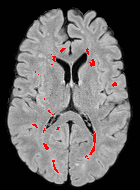

Patch size is another important parameter of the network. In computer vision applications such as object detection, usually a whole 2D image is used as a feature. However, full 3D medical images can not typically be used because of memory limitations. Fig. 4 shows examples of lesion memberships obtained with different sized 2D patches. As the patch sizes increases, the false positives that are mostly observed in the cortex tend to decrease. Fig. 5 shows a plot of Dice and LFPR with various patch sizes, ordered from left to right according to their increasing size. Note that smaller patches ( to ) produced significantly lower Dice and higher LFPR compared to other patches (), as seen from the memberships in Fig. 4. Also some of the highest Dice and lowest LFPR were observed for patches with large in-plane size, i.e., , , and . It was observed in Fig. 5 that there is no significant difference between Dice coefficients for , , or , but LFPR of both and are significantly lower than that of (). We chose as the optimal patch size. Other choices of smaller and patches (not shown) yielded worse results. Note that although training was performed with different patch sizes, the memberships were generated slice by slice, as the trained model consisted only of convolutions and did not need any information about patch sizes.

For this dataset, the training was performed separately with two sets of masks from the two raters of ISBI-21 data. Then two memberships were generated for each of the images. For each image, the two memberships were averaged and thresholded to form the final segmentation. Fig. 6 shows MR images and segmentations of subjects from the MS-100 dataset, where the subjects have high (cc), moderate (cc), and low (cc) lesion loads. For the subject with high lesion loads (#1), all methods performed comparably, although OASIS and LST underestimated some small and subtle lesions (yellow arrow). For the subject with moderate lesion load (#2), OASIS and S3DL underestimated some lesions (orange arrow) and LesionTOADS overestimated some (green arrow). When the lesion load is small and the FLAIR image has some artifacts (subject #3), LesionTOADS, S3DL, and OASIS produce a false positive (yellow arrow) in the cortex. LST shows underestimation, but FLEXCONN does not produce the false positive. The reason is partly because of the use of large patches, which can successfully distinguish between bright voxels in cortex and peri-ventricular regions.